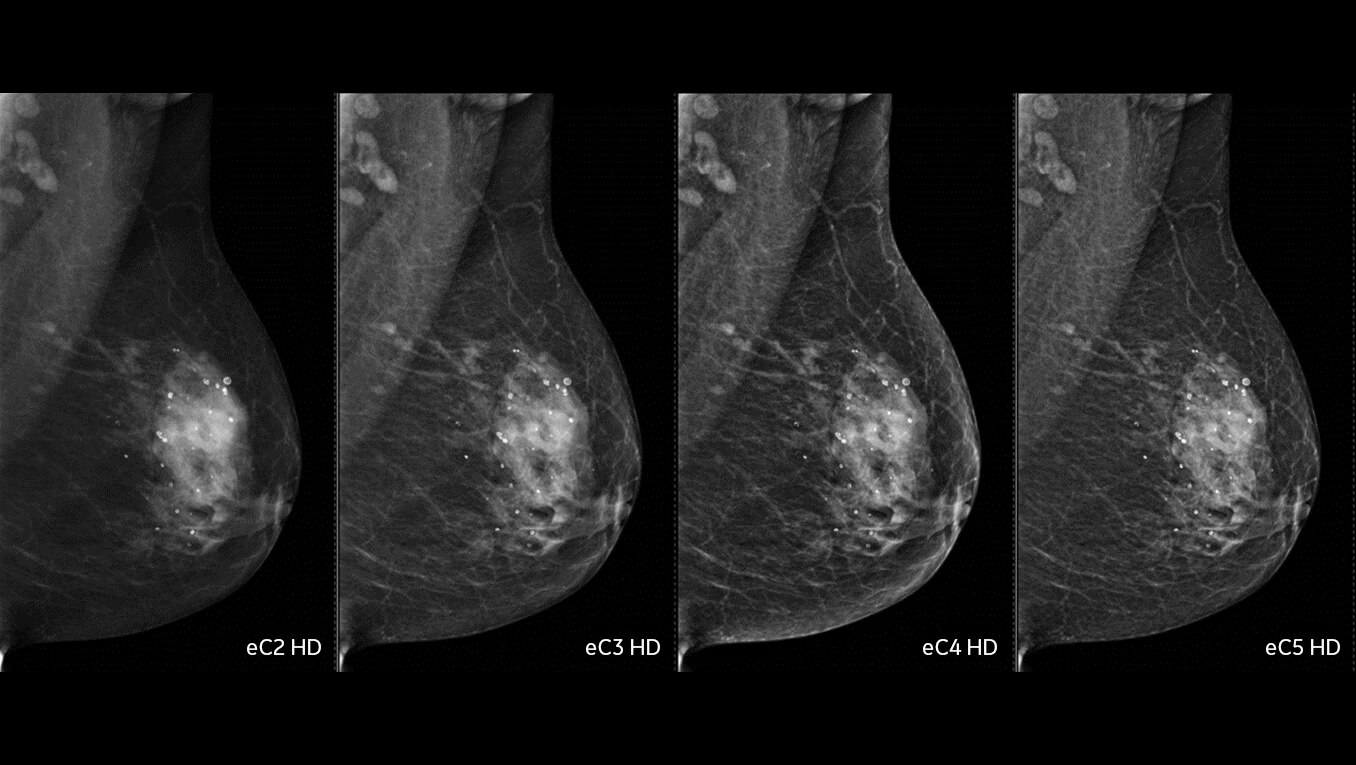

• 2D with eConstrast HD: the new processing improves the reading workflow by reducing the need to manually window our images and the radiologist confidence in our 2D image quality.

• 3D with Asir: reconstruction enables artifact management techniques that greatly reduces propagation of clips/microcalcs, at the expense of extra computation time (Asir is longer than FBP reconstruction.